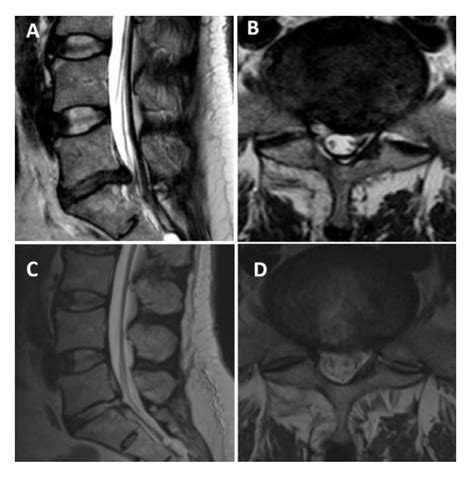

A paracentral disc protrusion is a type of herniated disc where the displaced disc material pushes out slightly to the side of the midline of the spinal canal. Unlike a central protrusion, which might affect the spinal cord itself, a paracentral protrusion is perfectly positioned to compress the nerve root as it exits the spine. This anatomical detail is crucial because the location of the disc material often dictates the specific symptoms a patient experiences, such as shooting pain, numbness, or tingling in a specific path along the arm or leg.

The spine is a complex structure, and the discs between the vertebrae are prone to wear and tear over time. Degenerative changes, sudden injuries, or repetitive strain can weaken the outer ring of the disc (the annulus fibrosus), allowing the inner, jelly-like center (the nucleus pulposus) to bulge out. Because the spinal canal has limited space, even a minor protrusion can result in significant neurological symptoms if it makes contact with sensitive neural tissues.

To confirm a paracentral disc protrusion, medical professionals rely on a combination of physical examinations and advanced imaging techniques. During a physical exam, a doctor will test your reflexes, muscle strength, and sensation levels to determine if a nerve root is being compromised.

Magnetic Resonance Imaging (MRI) The gold standard for visualizing soft tissues, nerves, and the extent of the disc protrusion.